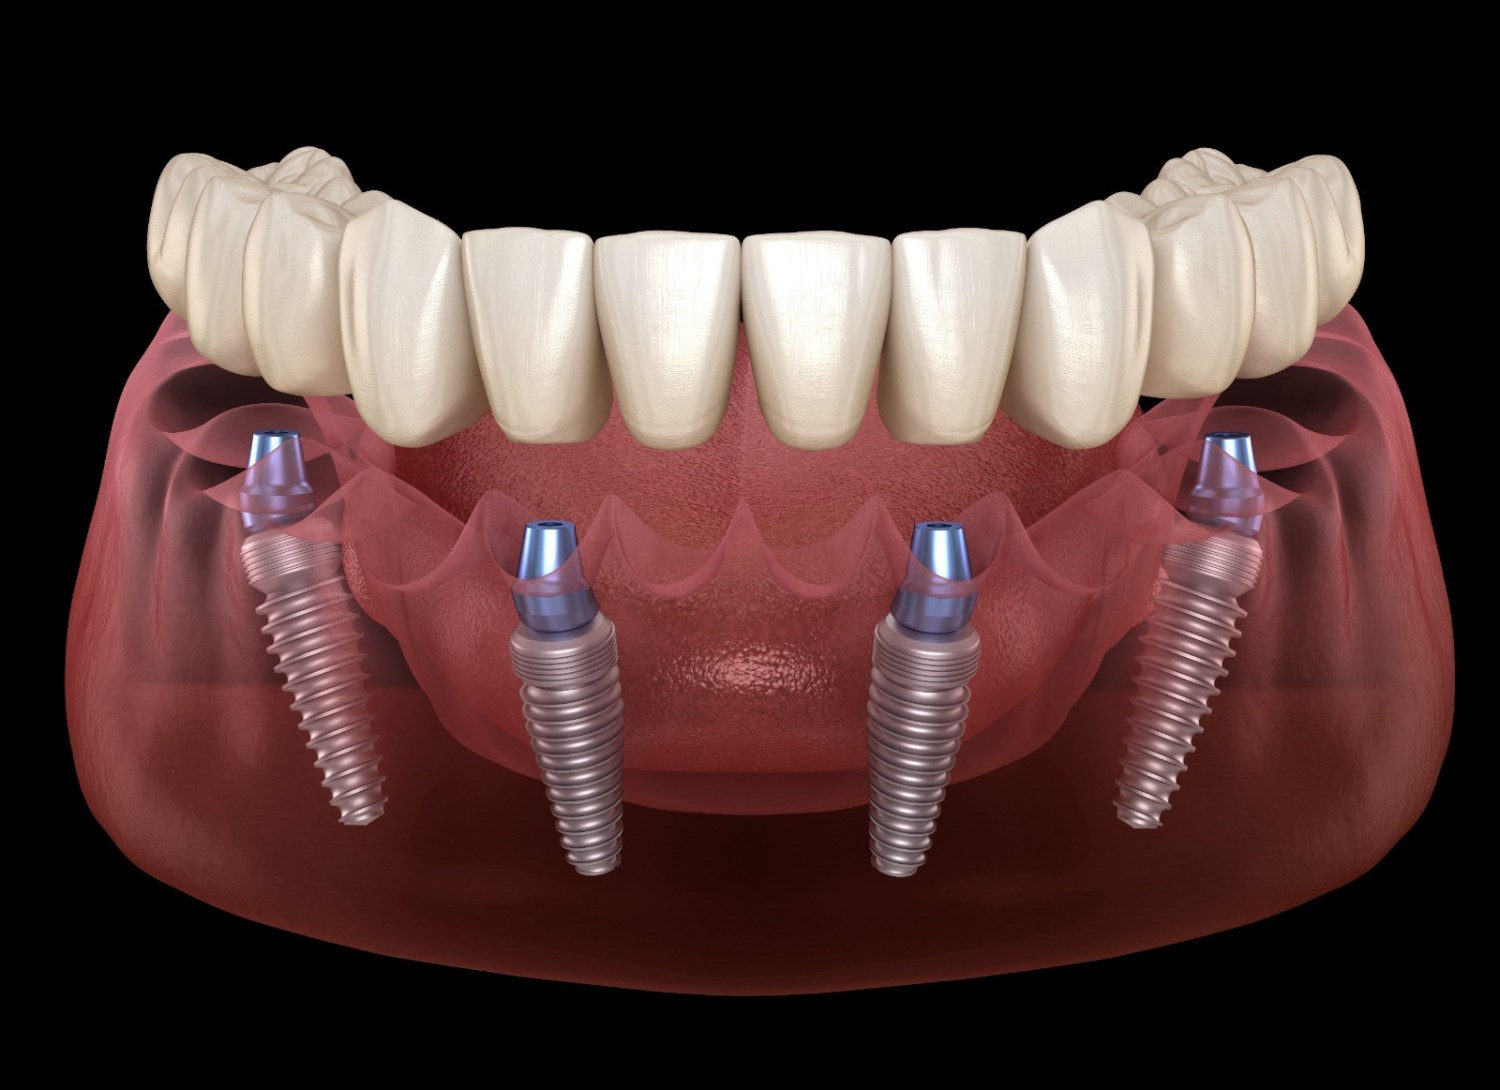

Dental crowns in Tijuana

Gum surgery in Tijuana